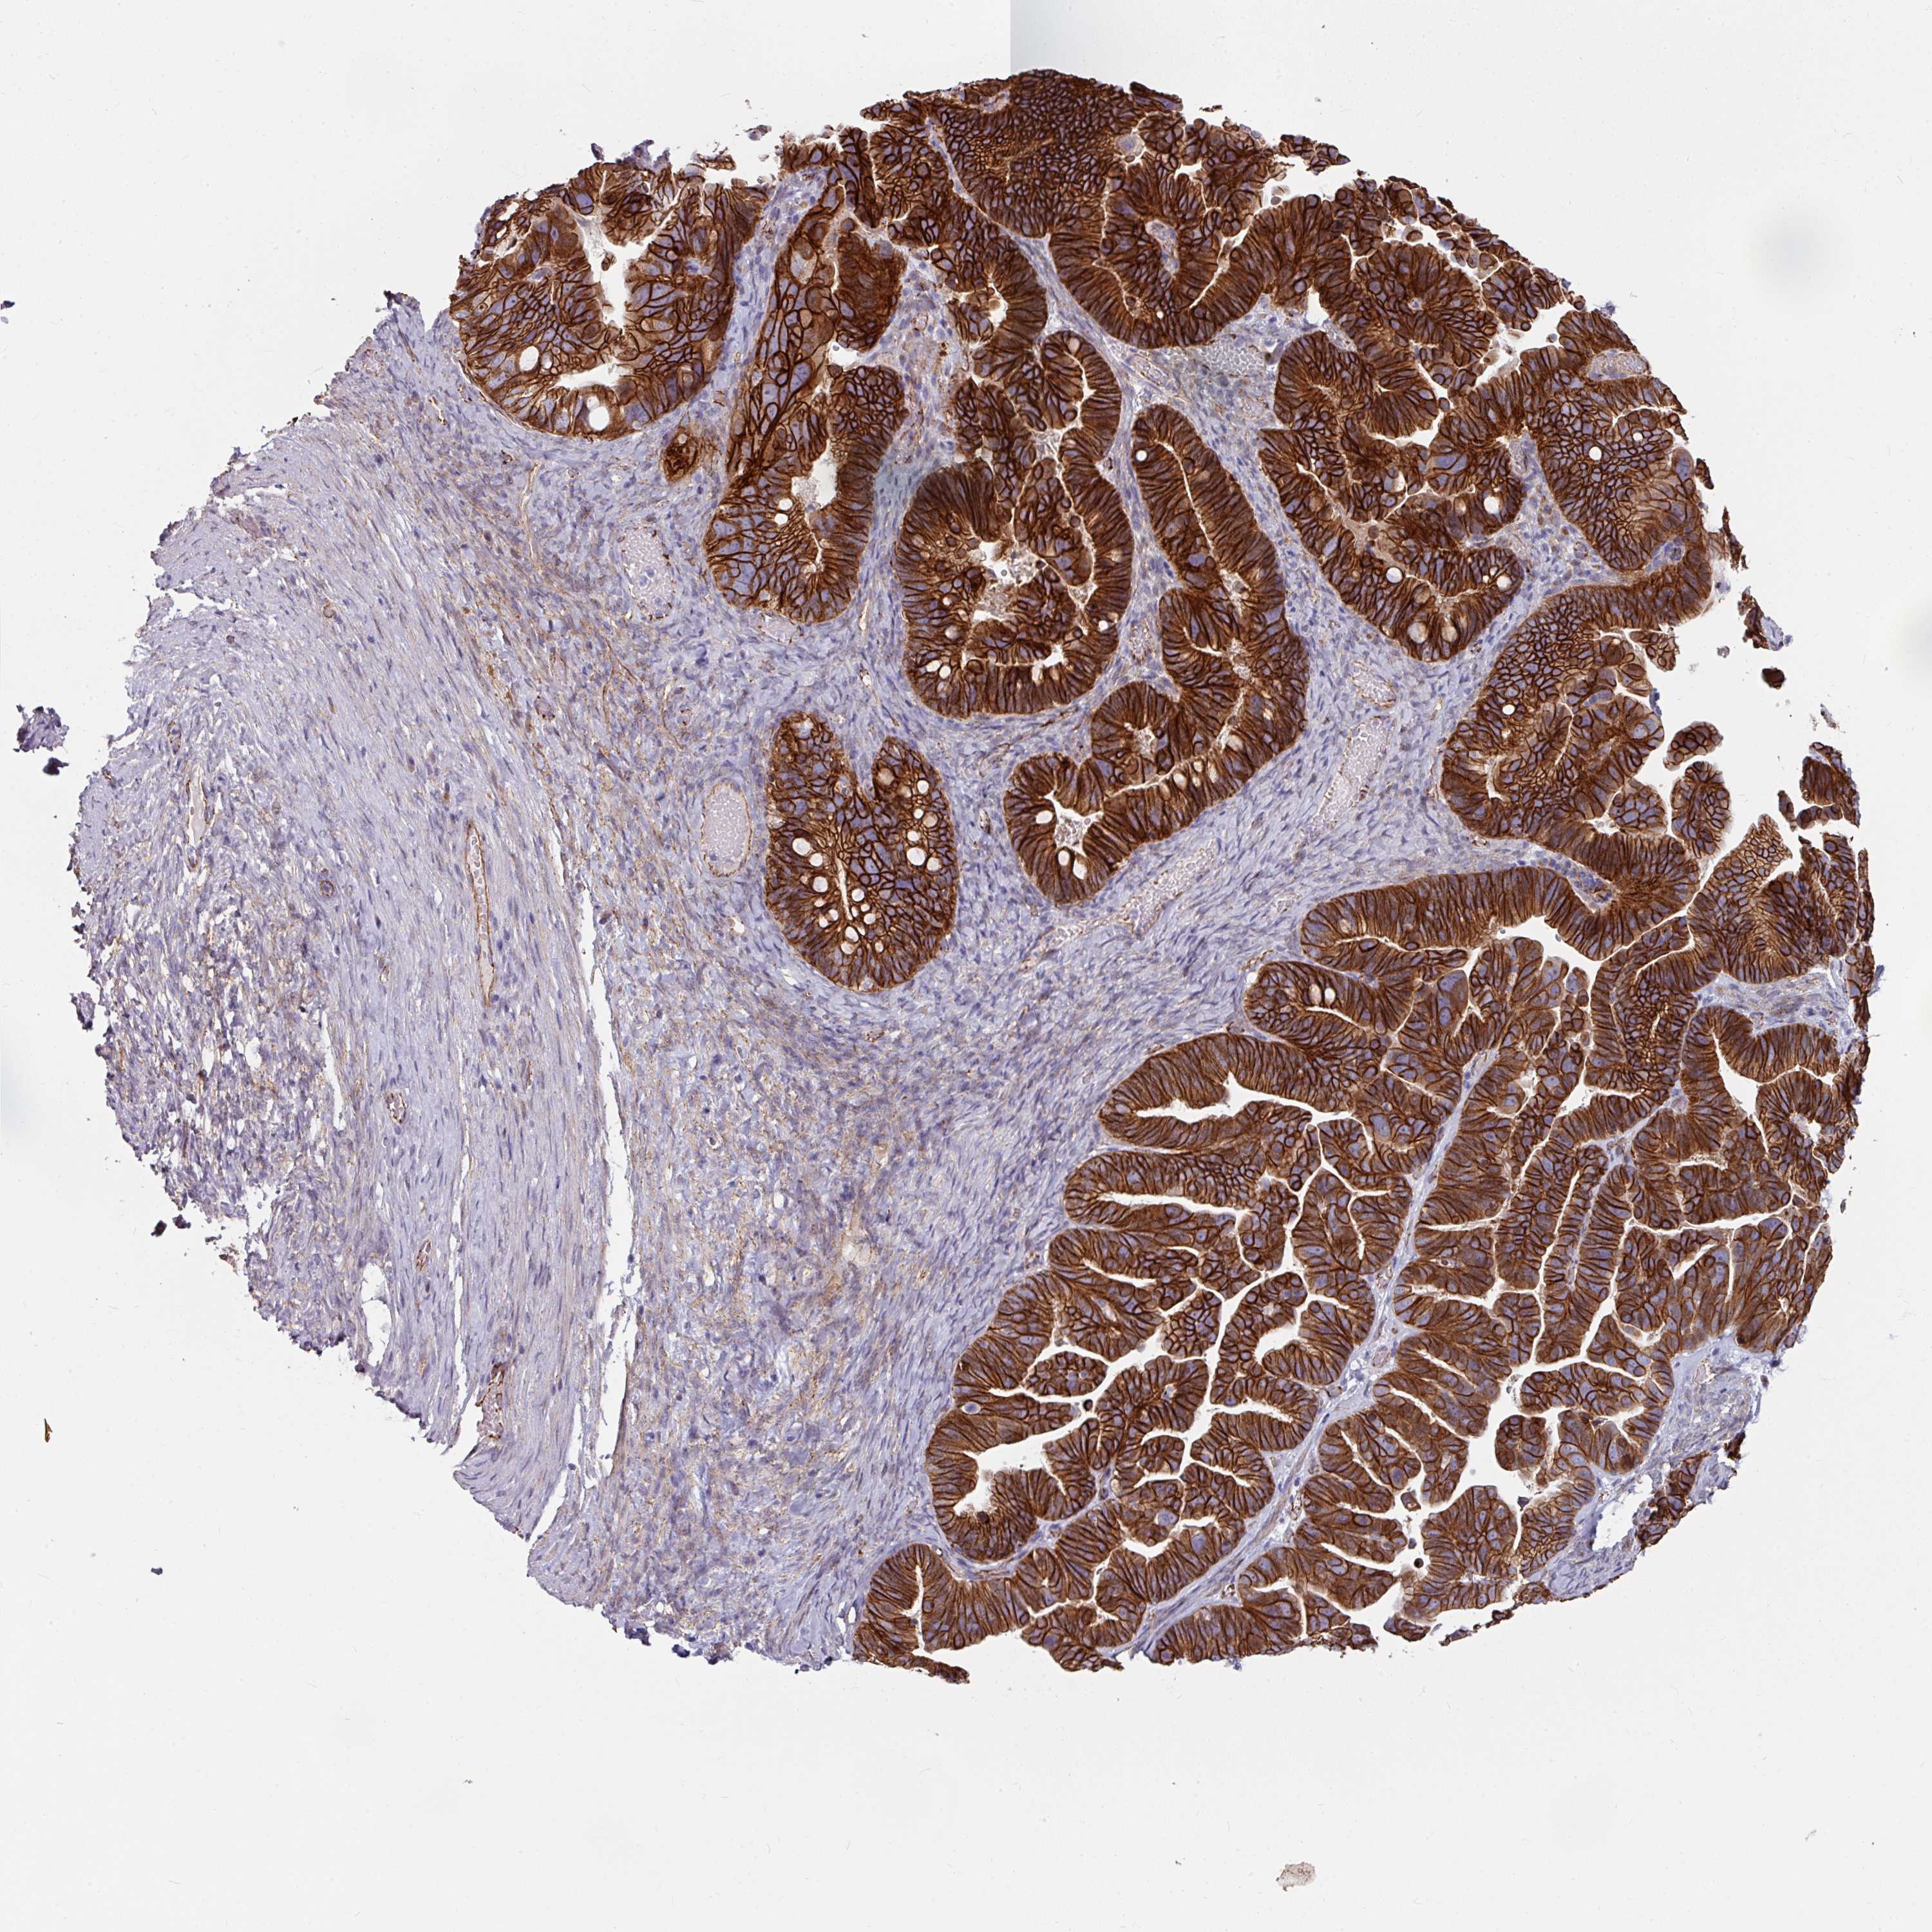

OVARIAN CANCER - Protein expressioni

A mouse-over function shows sample information and annotation data. Click on an image to view it in a full screen mode. Samples can be filtered based on level of antibody staining by selecting one or several of the following categories: high, medium, low and not detected. The assay and annotation is described here.

Note that samples used for immunohistochemistry by the Human Protein Atlas do not correspond to samples in the TCGA dataset.

Antibody stainingi

Antibody staining in the annotated cell types in the current human tissue is reported as not detected, low, medium, or high, based on conventional immunohistochemistry profiling in selected tissues. This score is based on the combination of the staining intensity and fraction of stained cells.

Each image is clickable and will lead to virtual microscopy that enables deeper exploration of all samples and also displays staining intensity scores, fraction scores and subcellular localization as well as patient and tissue information for each sample.

Antibody HPA032047

Antibody CAB002139

Cystadenocarcinoma, serous, NOS

Carcinoma, endometroid